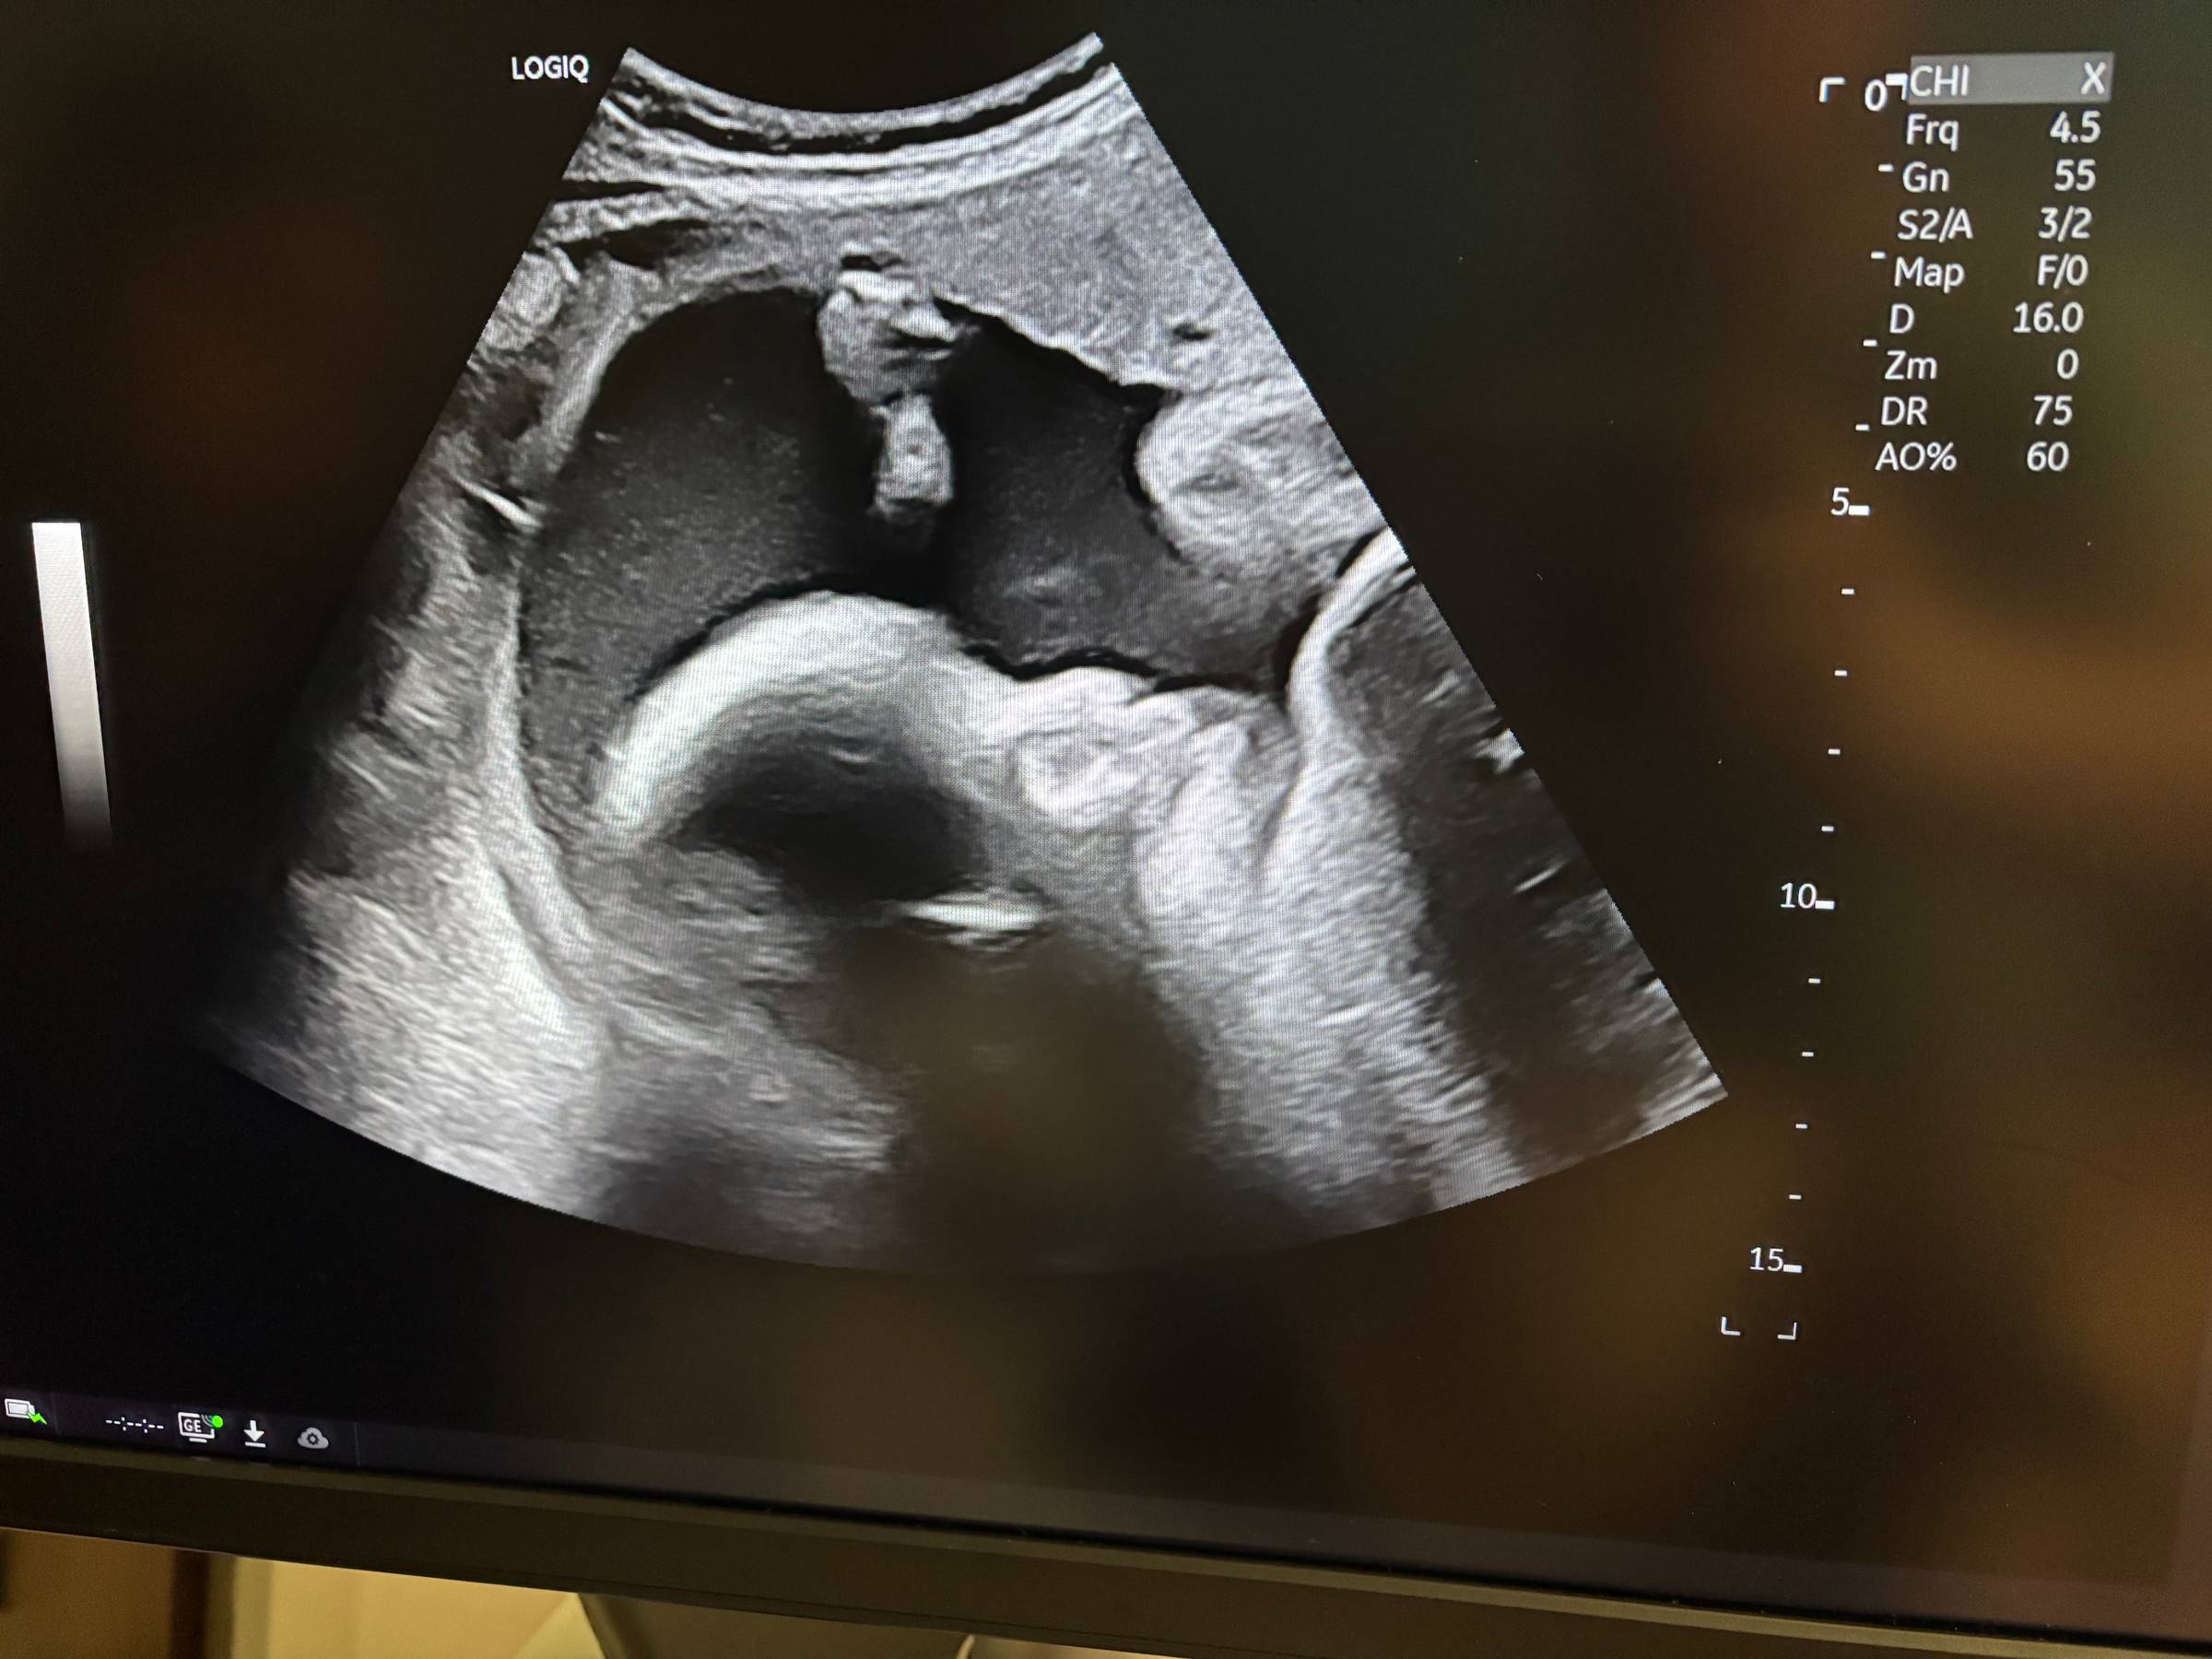

I tried counting kicks, but I wasn’t really sure about it. I felt movement, but wasn’t entirely sure. So, we went back the next morning. She still couldn’t find a heartbeat, so she advised us to go to the ER. We went home first, got the kids settled at Ian’s mom’s house, and then went to the ER, hoping for an ultrasound that showed everything was okay.

We got up to the room around 3pm, on Thursday, June 12th, and shortly after that we heard the news that left us shattered. At 32 weeks Myla was gone, probably since Tuesday evening, and there was nothing we could have done to change the outcome.